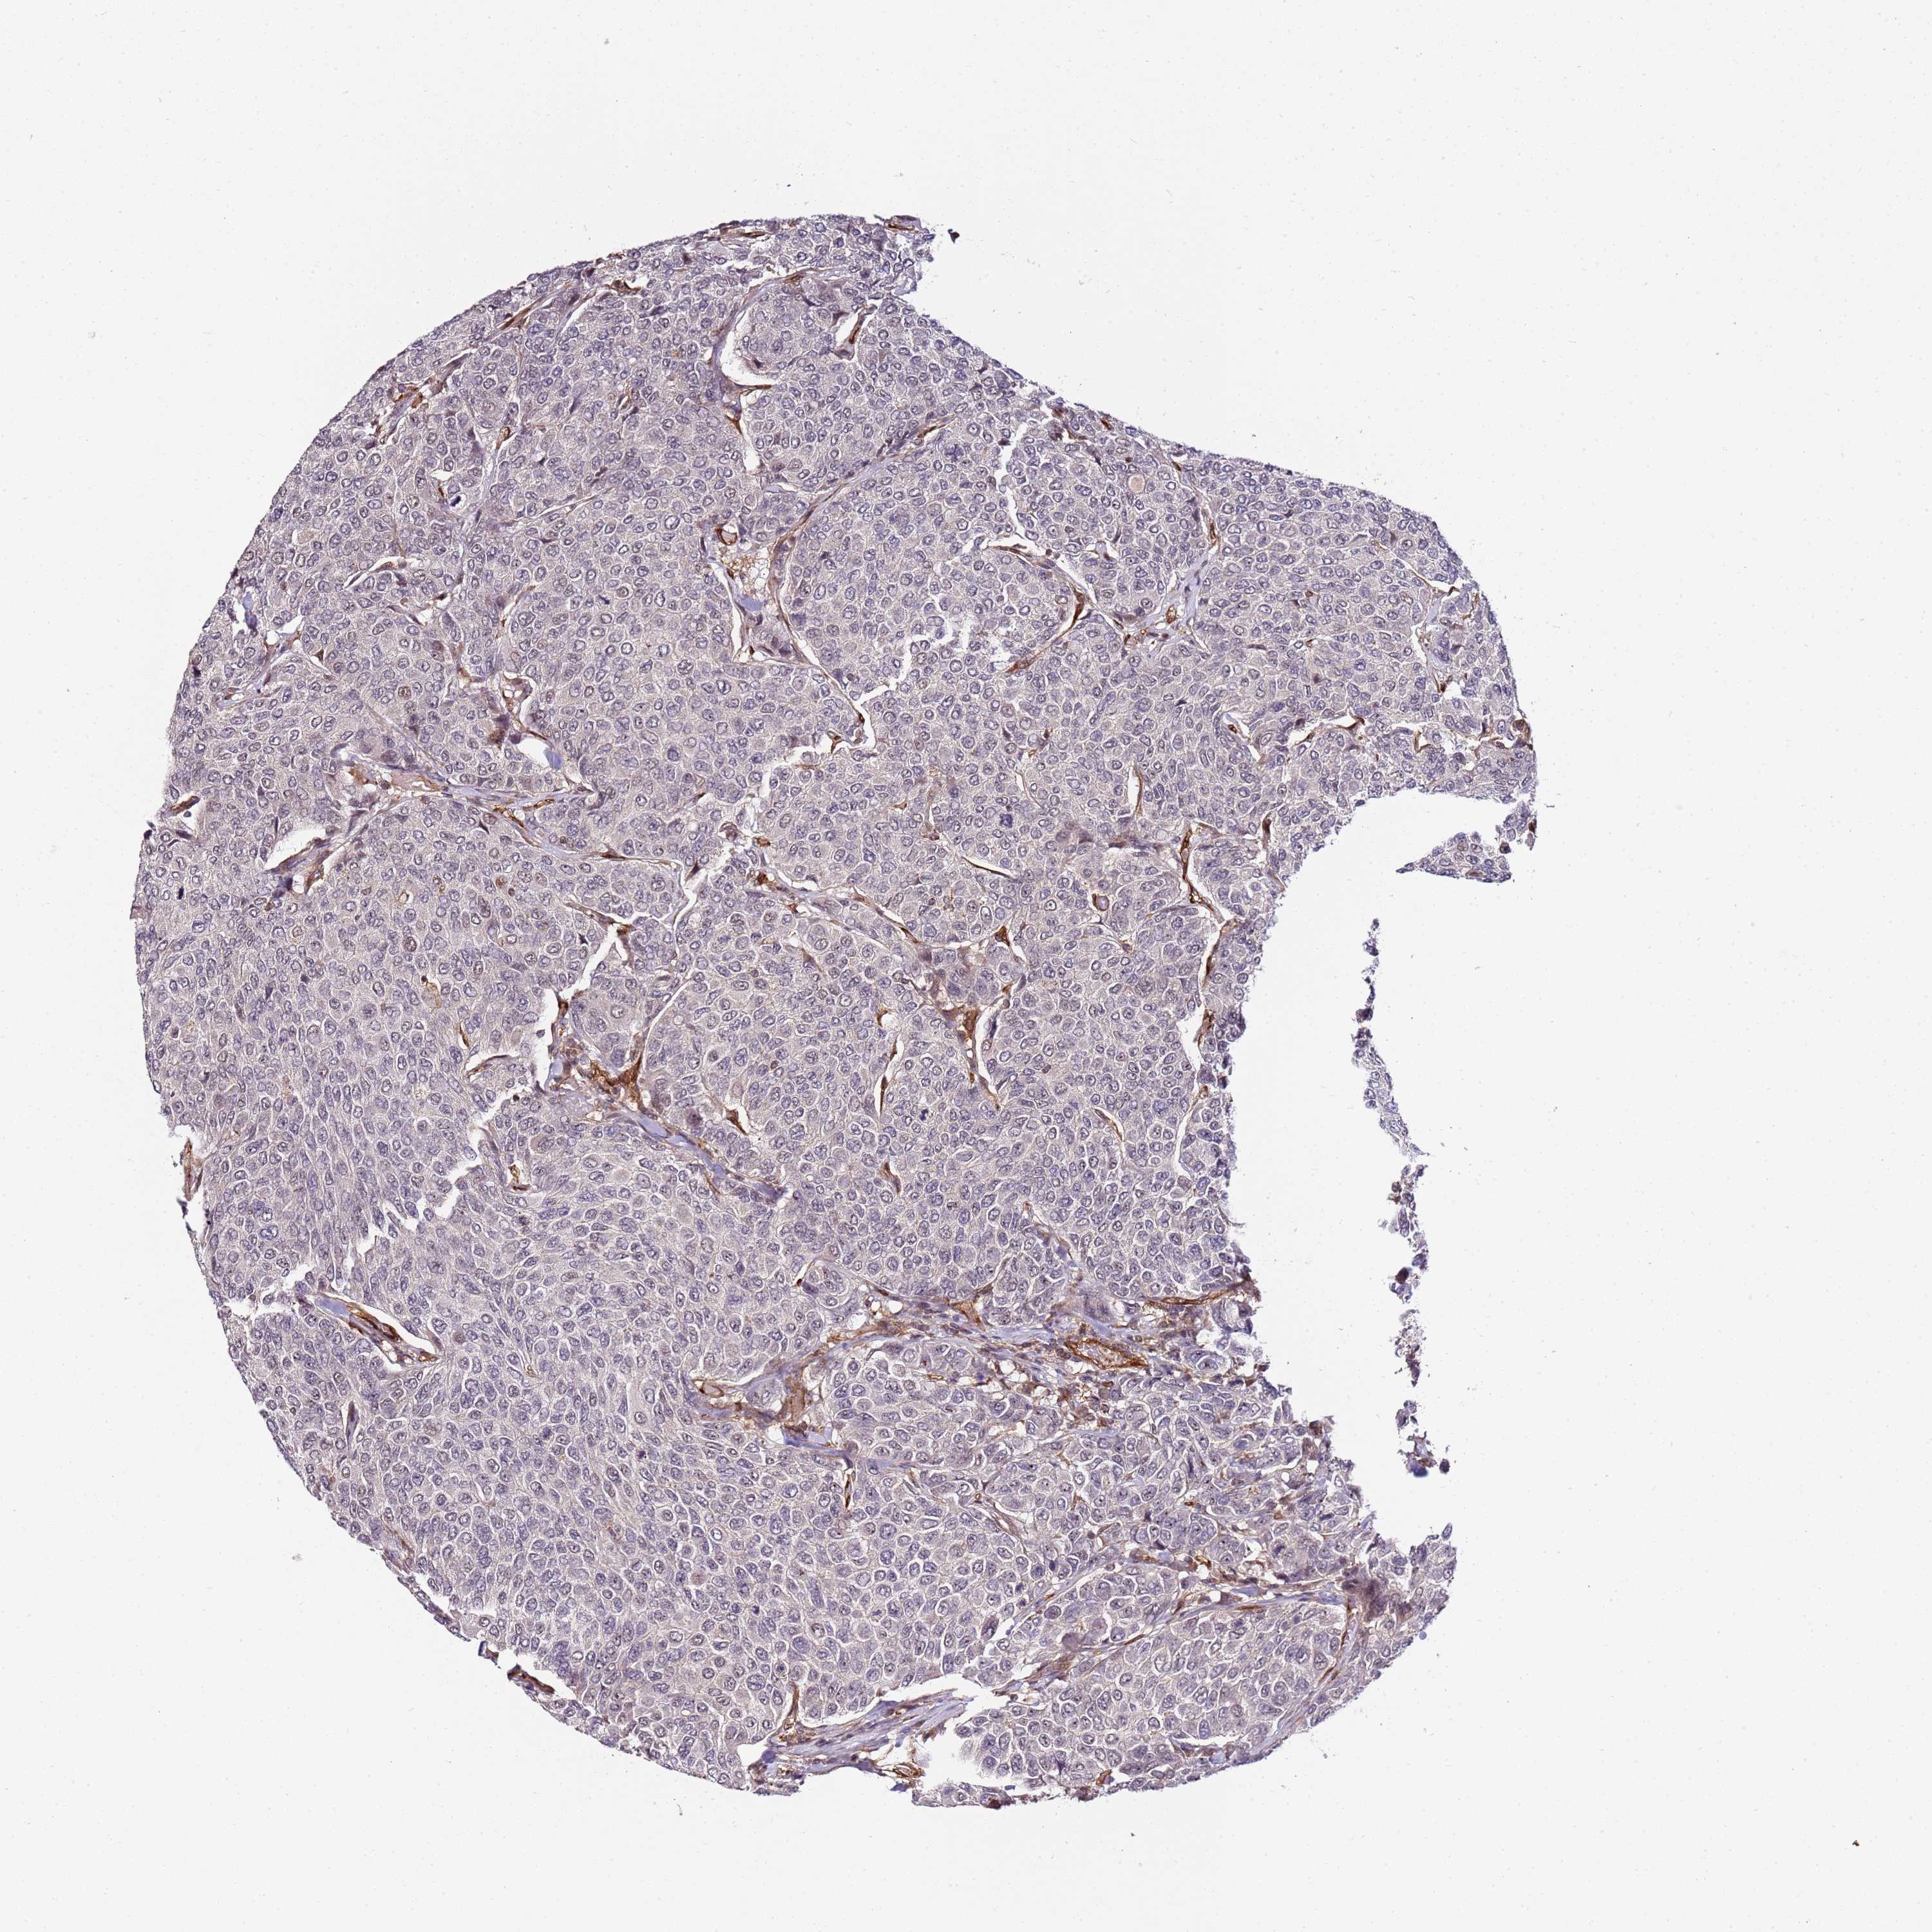

CANCER BREAST CANCER Show tissue menu

BRCA TCGA BRCA VALIDATION PROTEIN EXPRESSION